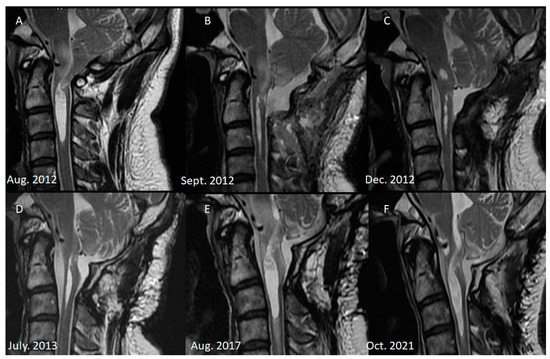

Over an 8-year follow-up period, the patient’s MRI examinations revealed that the syrinx had initially subsided by the 3-month postoperative MRI but subsequently progressed over the next 5 years (Figure 1). In the 8th year of follow-up, the patient returned with worsening symptoms, including intermittent neck and back pain, progressive left hemiparesis, and paresthesia lasting 6 months. Initially, the patient could walk with a cane. However, his ambulation gradually deteriorated, and he required a quadricane for walking support. In addition, he experienced numbness, clumsiness, and loss of grasp strength. His modified Japanese Orthopedic Association (mJOA) scale score was 10, and his Barthel Index score was 50. Neurological examination revealed a muscle strength of 4 in the right upper and lower extremities and a muscle strength of 2 in the left upper and lower extremities. Atrophy of the intrinsic hand muscles was observed along with hyperreflexia in all four limbs. However, no Hoffman’s or Babinski signs were detected, and no cranial nerve involvement was noted. Cervical myelopathy was suspected, and cervical spine MRI confirmed the progression of the syrinx, that is, confirmed that the syrinx had extended to the C4 level, with edematous changes in the spinal cord. No brain or thoracolumbar abnormalities were discovered, and no epidural mass at the craniocervical junction was observed.

Figure 1.

Series of cervical MRI. (A) Typical Chiari I malformation before decompressive surgery. (B) Due to transient dysphagia, we arranged a C-spine MRI 1 week after decompressive surgery. Mild edematous change over the medulla was observed, and short-term steroid administration was prescribed. Adequate decompression was achieved, and the syrinx shrunk. (C) CSF leakage was noted 3 months after the first surgery, for which dura repair was performed. MRI before the surgery revealed no signs of infection, and the syrinx length had decreased. (D) Six months after the revision surgery, MRI revealed mild progression of the syrinx and that the cord to the thecal sac was tethered. (E) In the 5th year of follow-up, the syrinx continued to progress and extended to the C3 level. Edematous change to the spinal cord was also observed. However, no clinical symptoms had developed. (F) In the 8th year of follow-up, progressive left side hemiparesis was observed, and MRI revealed syrinx extension to the C4 level, for which revision surgery was performed.